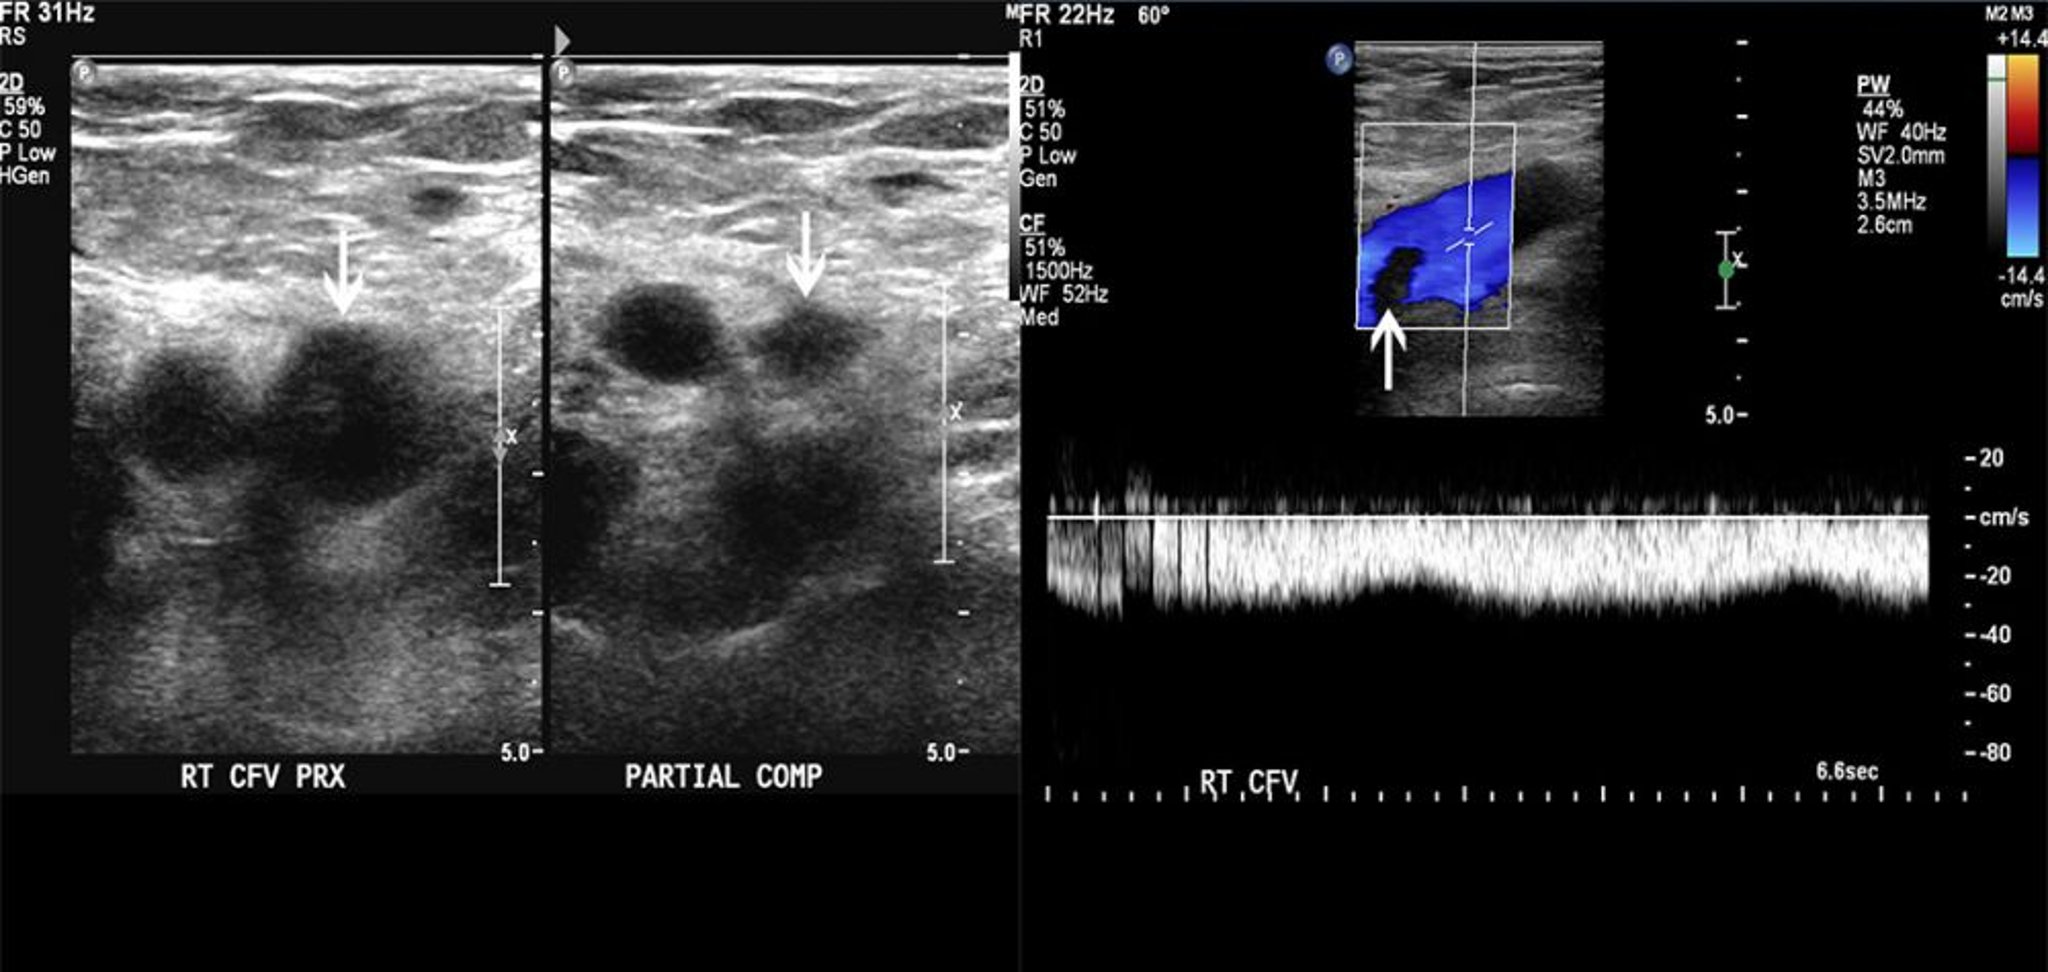

Échographie Doppler d'un patient qui a un thrombus dans la veine fémorale

L'image de gauche montre une compressibilité partielle de la veine fémorale commune (flèches). L'image de droite montre un défaut de remplissage du flux doppler couleur. Ces signes sont compatibles avec un thrombus.